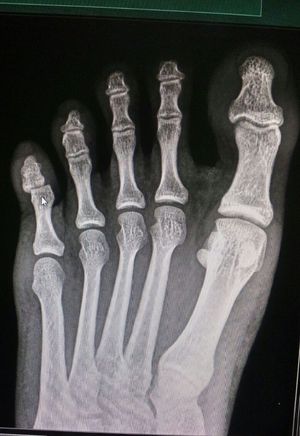

What is the diagnosis

The patient has sitting in wrong position on the little finger of left foot..

Dislocation

Little